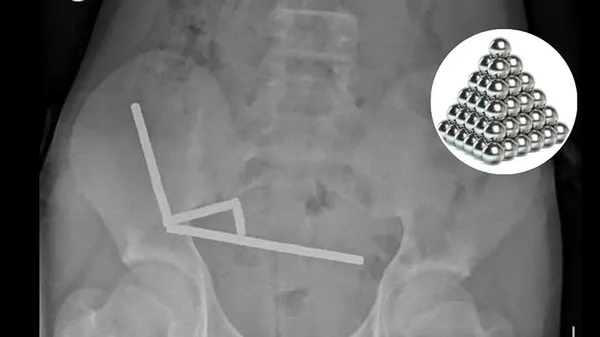

13-year-old boy swallows magnets: 13 ವರ್ಷದ ಬಾಲಕನೊಬ್ಬ ಇಂಟರ್ನೆಟ್‌ನಲ್ಲಿ ಇ-ಕಾಮರ್ಸ್ ಮಾರುಕಟ್ಟೆಯಿಂದ ಹೈ-ಪವರ್ ಅಯಸ್ಕಾಂತಗಳನ್ನು ಖರೀದಿಸಿ ನುಂಗಿರುವ ಆಘಾತಕಾರಿ ಘಟನೆ ನ್ಯೂಜಿಲ್ಯಾಂಡ್‍ನಲ್ಲಿ ನಡೆದಿದೆ. ಸರ್ಜರಿ ಮೂಲಕ 100ಕ್ಕೂ ಹೆಚ್ಚು ಆಯಸ್ಕಾಂತಗಳನ್ನು ವೈದ್ಯರು ಹೊರತೆಗೆದಿದ್ದಾರೆ.

ವೆಲ್ಲಿಂಗ್ಟನ್: 13 ವರ್ಷದ ಬಾಲಕನೊಬ್ಬ ಇಂಟರ್ನೆಟ್‌ನಲ್ಲಿ ಇ-ಕಾಮರ್ಸ್ ಮಾರುಕಟ್ಟೆಯಿಂದ ಹೈ-ಪವರ್ ಅಯಸ್ಕಾಂತಗಳನ್ನು ಖರೀದಿಸಿ ನುಂಗಿರುವ ಆಘಾತಕಾರಿ ಘಟನೆ ನ್ಯೂಜಿಲ್ಯಾಂಡ್‍ನಲ್ಲಿ (New Zealand) ನಡೆದಿದೆ. 100 ಕ್ಕೂ ಹೆಚ್ಚು ಅಯಸ್ಕಾಂತಗಳನ್ನು (Magnets) ನುಂಗಿದ ನಂತರ ಬಾಲಕ ಶಸ್ತ್ರಚಿಕಿತ್ಸೆಗೆ ಒಳಗಾಗಬೇಕಾಯಿತು. ಈ ವೇಳೆ ವೈದ್ಯರು ಅವನ ಕರುಳಿನ ಒಂದು ಭಾಗವನ್ನು ತೆಗೆದುಹಾಕಬೇಕಾಯಿತು. ಈ ಸುದ್ದಿ ಇದೀಗ ವೈರಲ್ (Viral News) ಆಗಿದೆ.

2014 ರಿಂದ ದೇಶೀಯ ಅಥವಾ ವೈಯಕ್ತಿಕ ಬಳಕೆಗಾಗಿ ಸಣ್ಣ, ಹೈ-ಪವರ್ ಅಯಸ್ಕಾಂತಗಳ ಮಾರಾಟವನ್ನು ನ್ಯೂಜಿಲ್ಯಾಂಡ್ ನಿಷೇಧಿಸಿದ ನಂತರವೂ ಈ ಆತಂಕಕಾರಿ ಘಟನೆ ಸಂಭವಿಸಿದೆ. ಜನಪ್ರಿಯ ಆನ್‌ಲೈನ್ ಮಾರುಕಟ್ಟೆಯಾದ ಟೆಮುನಿಂದ ಆರ್ಡರ್ ಮಾಡಿದ್ದ 100ಕ್ಕೂ ಹೆಚ್ಚು ಆಯಸ್ಕಾಂತಗಳನ್ನು ಬಾಲಕ ನುಂಗಿದ್ದ. ಶಸ್ತ್ರಚಿಕಿತ್ಸೆಗೆ ಒಂದು ವಾರದ ಮೊದಲು ಆ ಹದಿಹರೆಯದ ಬಾಲಕ ಸುಮಾರು 80 ರಿಂದ 100 ಸಣ್ಣ ಆಯಸ್ಕಾಂತಗಳನ್ನು ನುಂಗಿದ್ದ ಎಂದು ಟೌರಂಗಾ ಆಸ್ಪತ್ರೆಯ ಶಸ್ತ್ರಚಿಕಿತ್ಸಕರು ತಿಳಿಸಿದಿದ್ದಾರೆ. ಅವೆಲ್ಲವನ್ನೂ ಬಾಲಕ ಆನ್ಲೈನ್ ಮಾರುಕ್ಟಟೆಯಾದ ಟೆಮುವಿನಲ್ಲಿ ಖರೀದಿಸಿದ್ದನು.

ನಾಲ್ಕು ದಿನಗಳ ಕಾಲ ಸಾಮಾನ್ಯ ಹೊಟ್ಟೆನೋವಿನಿಂದ ಆಸ್ಪತ್ರೆಗೆ ದಾಖಲಾದ 13 ವರ್ಷದ ಬಾಲಕನ ಪ್ರಕರಣವನ್ನು ನಾವು ಪರಿಶೀಲಿಸುತ್ತಿದ್ದೇವೆ ಎಂದು ವೈದ್ಯರ ತಂಡ ಹೇಳಿತ್ತು. ಬಾಲಕ ಸುಮಾರು ಒಂದು ವಾರದ ಹಿಂದೆ ಸುಮಾರು 80–100 5x2mm ಹೈ-ಪವರ್ (ನಿಯೋಡೈಮಿಯಮ್) ಆಯಸ್ಕಾಂತಗಳನ್ನು ಸೇವಿಸಿದ್ದಾಗಿ ಬಹಿರಂಗಪಡಿಸಿದ್ದಾನೆ. ಇವುಗಳನ್ನು ವಿದೇಶಿ ಆನ್‌ಲೈನ್ ಮಾರುಕಟ್ಟೆಯಿಂದ (ಟೆಮು) ಖರೀದಿಸಲಾಗಿತ್ತು.